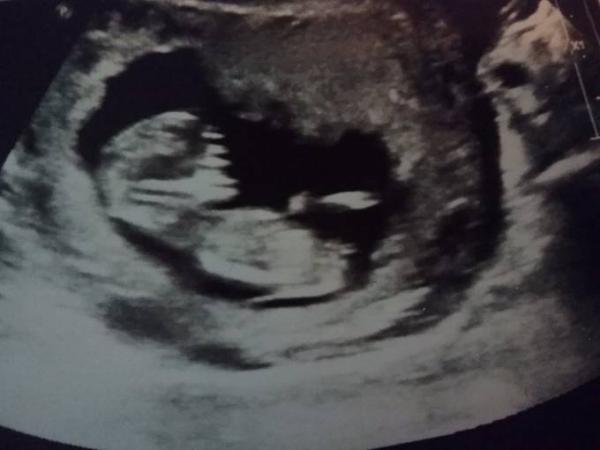

Es ist alles super entwickelt bei unserem Würmchen. Ich wurde vordatiert auf den 25.6. 2018 unser Baby ist schon 5,4cm gross....Wahnsinn!! Also bin ich jetzt laut Arzt 12+1ssw (13ssw)

Nackenfalte sah unauffällig aus, was mich schon mal beruhigt.

Hier noch ein Bildchen